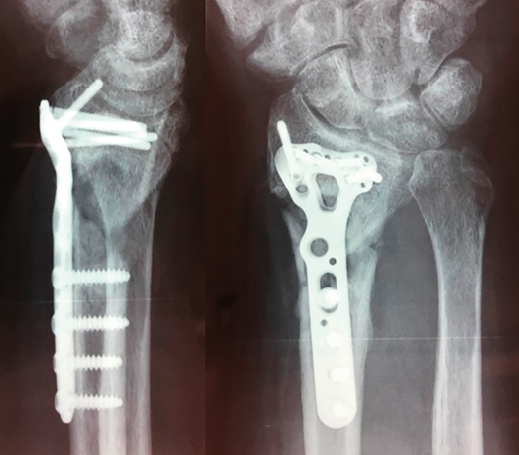

Figura 3. Ausencia de consolidación establecida, 6 meses de la fractura.

A los 6 meses no existió progreso radiológico y la falta de consolidación se manifestó claramente con pérdida de la reducción progresiva y dolor (Figura 3). En ese momento, se realizó la segunda cirugía abierta: extracción del material de síntesis que presentaba tornillos distales rotos (los bloqueados) y aflojados el resto, toma de muestras para cultivo, toma de muestra para anatomía patológica, limpieza del foco, perforación del hueso distal y proximal, colocación de autoinjerto tricortical estructural impactado y esponjosa de la cresta ilíaca y nueva síntesis con placa Acu-Loc 2® distal estándar larga de Acumed. Se consiguió restituir aceptablemente la longitud del radio respecto a la articulación radiocubital distal, quedando cierta traslación radial y extensión que provocaba una protrusión volar de la zona distal de la placa conformada. No se realizó intervención en la articulación radiocubital distal, ya que no presentaba ni inestabilidad ni dolor significativos, ni signos artrósicos francos.